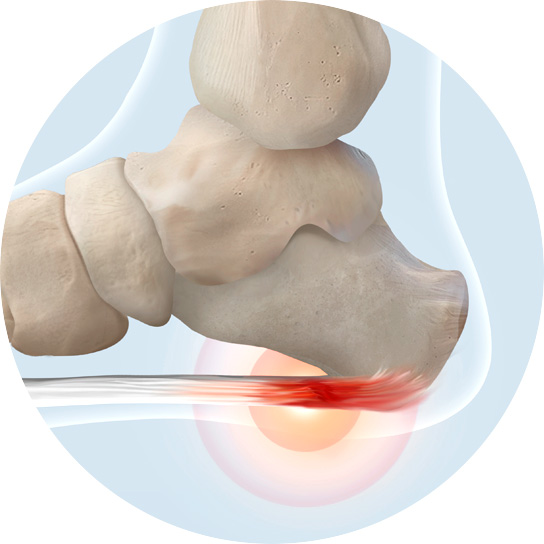

발바닥을 감싸는 두꺼운 섬유 조직인 족저근막에 발생하는

건병증입니다. 족저근막은 발뒤꿈치 뼈에서 발가락까지 이어져

있으며 발의 아치를 유지하고 충격을 흡수하는 역할을 합니다.

족저근막염은 과도한 사용, 부적절한 신발 착용, 발의 구조적

이상 등으로 인해 발생할 수 있습니다.